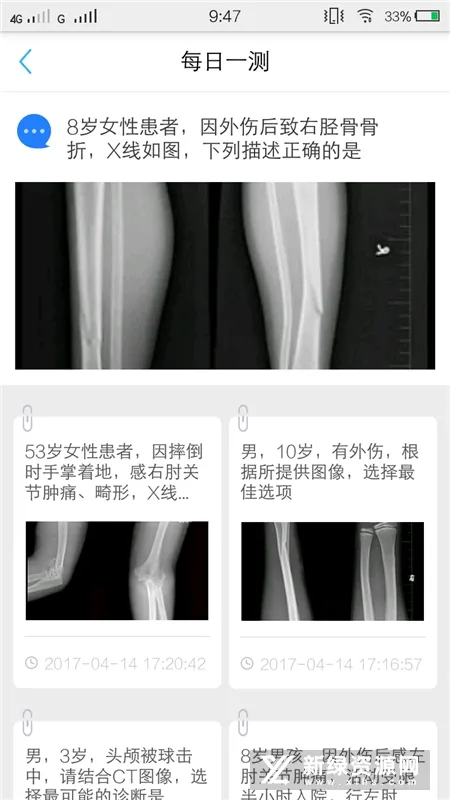

3. 病例管理分享:可使用病例采集功能,利用手机拍照、图文识别等方式快速记录和上传优秀病例,并和同行进行病例讨论分享。

3. 病例管理分享:能利用手机拍照、图文识别等方式快速记录和上传优秀病例,并与同行进行病例讨论分享。